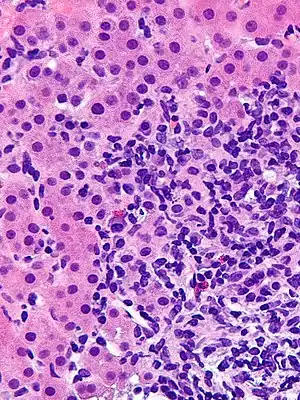

Micrograph showing a lymphoplasmacytic interface hepatitis—the characteristic histomorphologic finding of autoimmune hepatitis. Liver biopsy. H&E stain.

Autoimmune hepatitis can be characterized histologically by the following nonspecific findings:[13][14][15][16]

• Portal mononuclear cell infiltrate that invades the boundary surrounding the portal triad and infiltrates the surrounding lobule.

• Periportal lesions, also known as interface hepatitis, that spare the biliary tree (may include centrizonal necrosis).

• Bile duct abnormalities (cholangitis, ductal injury, ductular reaction) can be seen and should prompt evaluation for primary biliary cholangitis or sarcoidosis if granulomas are observed.

• Plasma cell infiltrate, rosettes of hepatocytes, and multinucleated giant cells.

• Varying degrees of fibrosis (except in the mildest form of autoimmune hepatitis). Bridging fibrosis that connects the portal and central areas can distort the structure of the hepatic lobule and result in cirrhosis.